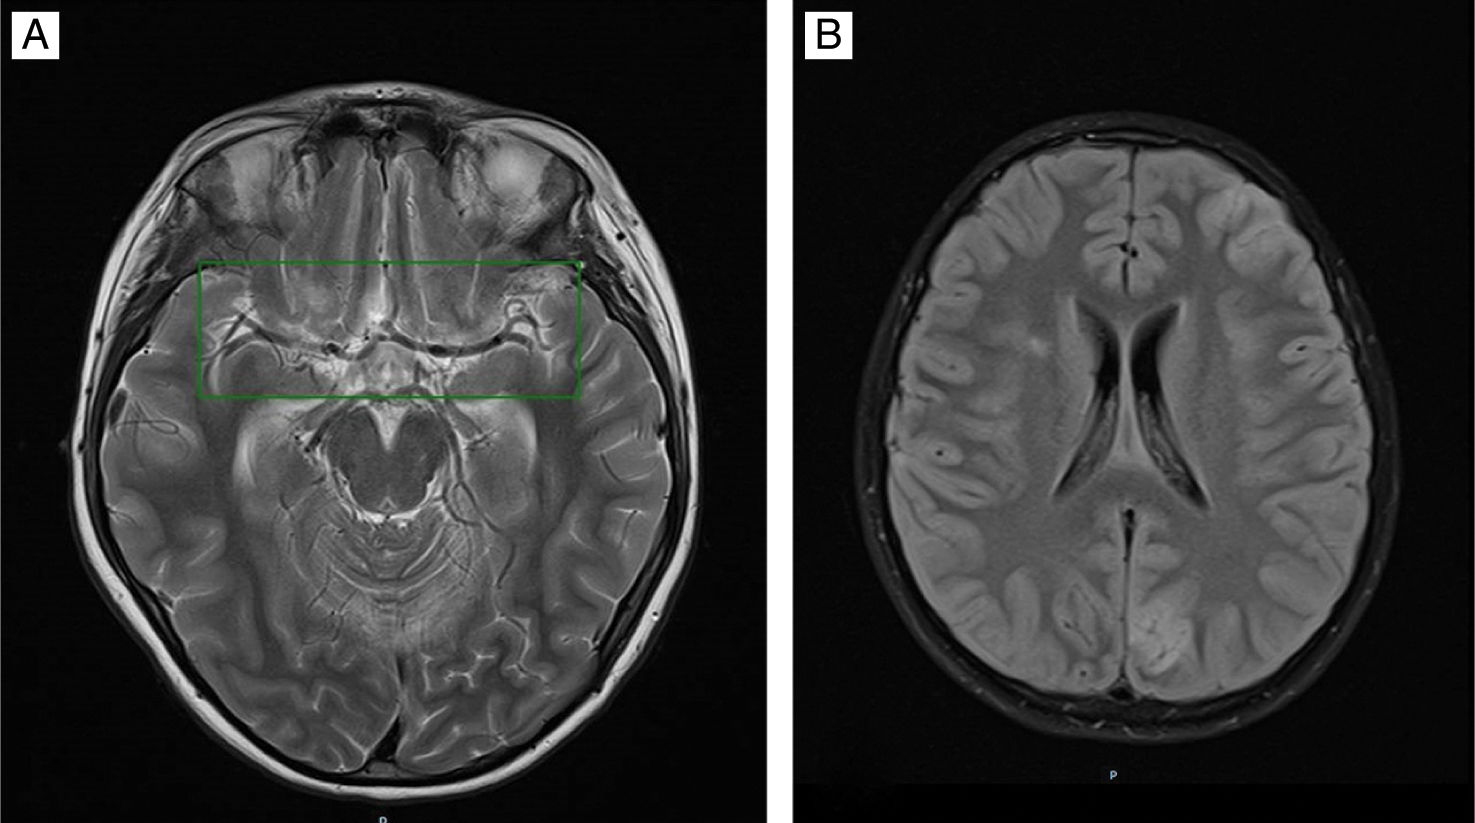

Given the poor response, a magnetic resonance (MR) scan was requested (Fig. 1A) that showed signs of infratentorial meningitis (Fig. 1B), generalised ventriculitis and supratentorial ischaemic encephalitis. At 5 days, once symptoms had improved, the patient was extubated and exhibited flaccid paraparesis with absent reflexes and numbness and cauda equina syndrome. The MRI of the scan was compatible with transverse myelitis1 (Fig. 2A) and evinced the presence of purulent material in the thecal sac with cauda equina radiculitis2 and arachnoiditis (Fig. 2B).

T2-weighted MRI of the brain, horizontal view, showing: (A) Abnormal signal intensity of sulci at supratentorial level. (B) Abnormal signal intensity with pathological restriction of the ependyma of both occipital horns and the third ventricle and mild restriction of the ependyma of the fourth ventricle, with purulent material at the downward slope of both occipital horns.